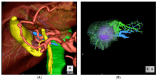

Laparoscopic liver resections have gained widespread popularity among hepatobiliary surgeons and is nowadays performed for both standard and more complex hepatectomies. Given the increased technical challenges, preoperative planning and intraoperative guidance is pivotal in laparoscopic surgery to safely carry out complex and oncologically safe hepatectomies. Modern tools can help both preoperatively and intraoperatively and allow surgeons to perform more precise hepatectomies. Preoperative 3D reconstructions and printing as well as augmented reality can increase the knowledge of the specific anatomy of the case and therefore plan the surgery accordingly and tailor the procedure on the patient. Furthermore, the indocyanine green retention dye is an increasingly used tool that can nowadays improve the precision during laparoscopic hepatectomies, especially when considering anatomical resection. The use of preoperative modern imaging and intraoperative indocyanine green dye are key to successfully perform complex hepatectomies such as laparoscopic parenchymal sparing liver resections. In this narrative review, we discuss the aspects of preoperative and intraoperative tools that are nowadays increasingly used in experienced hepatobiliary centers.